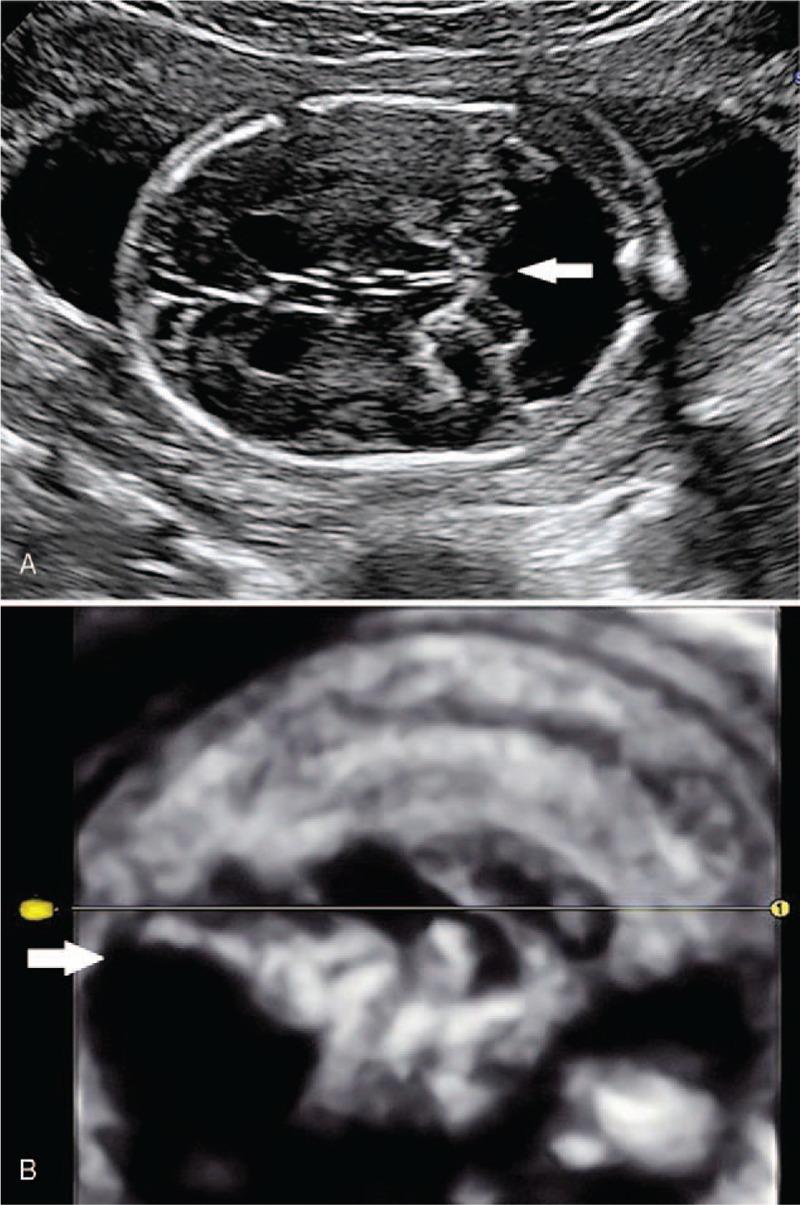

The prenatal phenotype of case 1 included sonographic markers such as enlarged nuchal translucency (NT), absent nasal bone, short femur and humerus length, and several structural malformations involving Dandy-Walker malformation and congenital heart defects. The prenatal phenotype of Case 2 are sonographic markers, including enlarged NT, thickened nuchal fold, ascites, and polyhydramnios without apparent structural malformations.

Conventional G-band karyotype appears normal in case 1, while it shows normal chromosomes with a small supernumerary marker chromosome (sSMC) in case 2. Genetic etiology was left unknown until single-nucleotide polymorphism-based array (SNP-array) was performed, and segmental paternal UPD 22 was identified in case 1 and segmental paternal UPD 14 was found in case 2.